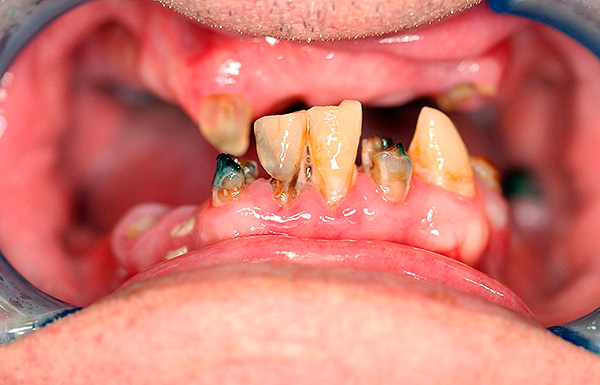

Exemplo 1, antes do tratamento:

Exemplo 2, foto antes do tratamento: